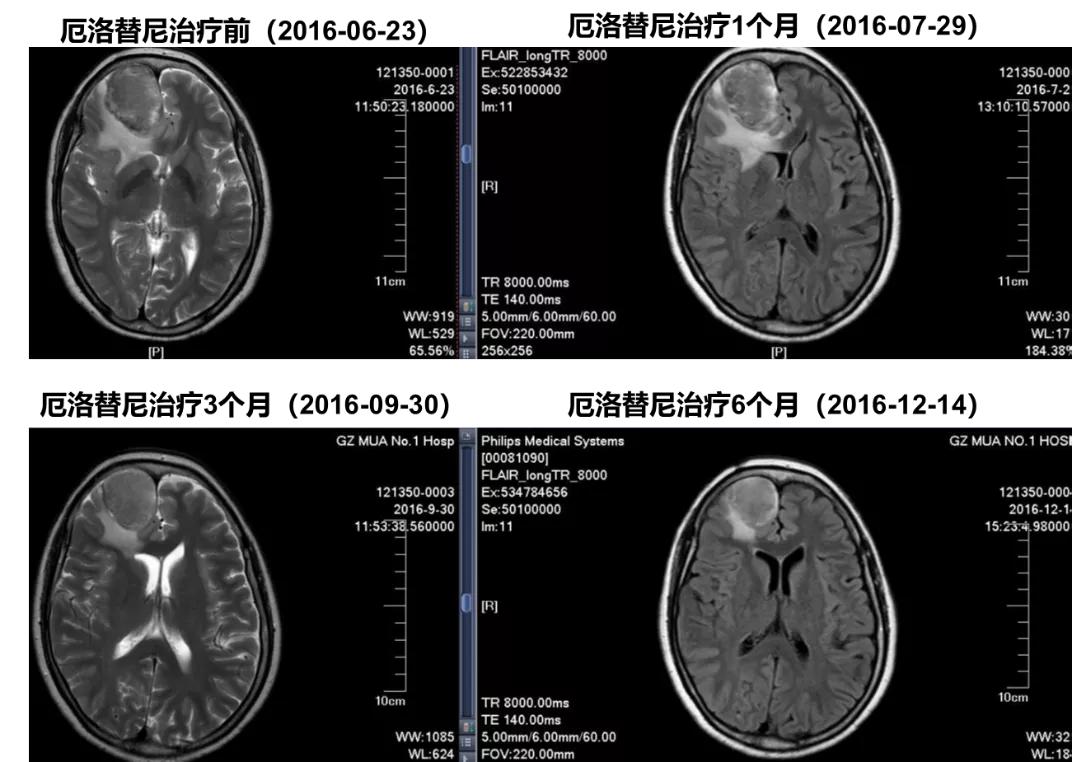

头颅MRI诊断:

1.考虑双侧额叶、左侧顶叶皮层多发转移瘤,双侧侧脑室前角及胼胝体膝部受压。

2.右侧筛窦少许炎症。

脑部MRI显示:双侧额叶、左侧顶叶皮层多发转移瘤,双侧侧脑室前角及胼胝体膝部受压。

厄洛替尼一线治疗患者MRI随访

脑部MRI显示:厄洛替尼治疗6个月期间右侧额部病灶持续缩小至PR。